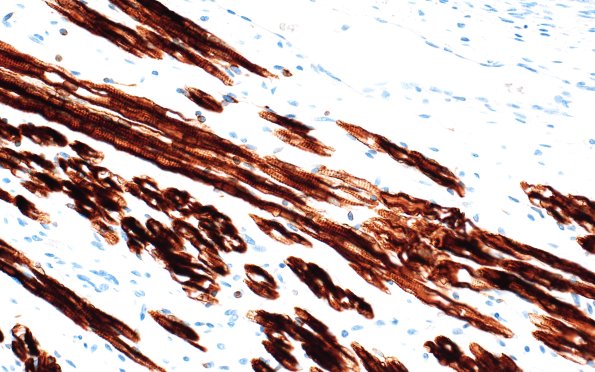

1T3 Teratoma, immature (Case 1) Desmin 40X

Desmin highlights the striations in this group of muscle cells. (Desmin IHC)